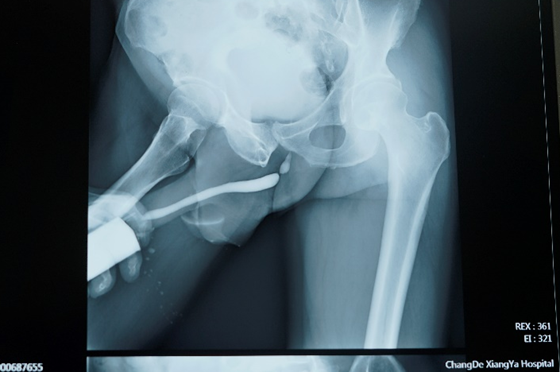

泌尿外科主任顿金庚教授团队接诊后,仔细询问病史,结合患者外伤史、输尿管镜检及术前逆行造影片,明确患者为典型的尿道球部狭窄,制定手术方案,拟行“舌粘膜扩大尿道球部成形术”。

尿道狭窄是泌尿外科的常见病之一,常见病因为外伤(骑跨伤、骨盆骨折)、医源性、感染等,主要表现为尿频、排尿费力、尿线变细,甚至尿潴留、上尿路积水感染等。术前病史、体格检查很重要,尿道造影是术前诊断主要检查。如出现排尿困难,请及时前往泌尿外科就诊。